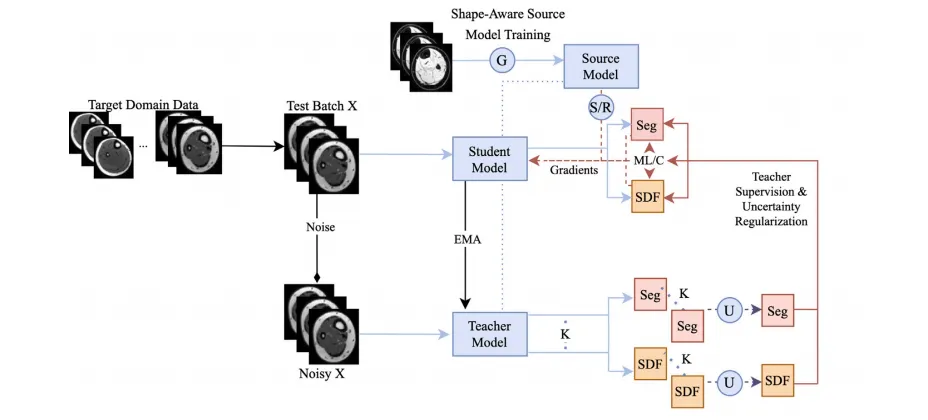

The proposed framework is a synergy of four components (Fig. 2)🙁1) shape-aware model training, (2) shape and uncertainty-aware meanteacher network, (3) multi-level cross-task consistency regularizationwith uncertainty ranking, and (4) domain-generalized stochastic weightrestoration for continual adaptation. Component (1) is used for modeltraining in the source domain, while (2) - (4) are used simultaneouslyfor CTTA. We describe each component in detail below.

提出的框架由四个组成部分协同构成(图2): (1) 形状感知模型训练; (2) 形状与不确定性感知的平均教师网络; (3) 带有不确定性排序的多级跨任务一致性正则化; (4) 面向持续适应的域泛化随机权重恢复。

组件(1)用于在源域中进行模型训练,而组件(2)-(4)则同时用于CTTA(持续测试时适应)。以下将详细描述每个组件的功能与设计。

Fig. 2. Schematic of the proposed CTTA framework. The model is first trained on the source domain with shape-aware DG techniques for generalizable and adaptable baseline performance. Then, a multi-task uncertainty-weighted mean teacher network adapts the student model to an unseen and unlabeled target domain via uncertainty-weighted pseudopredictions produced by the teacher model. Meanwhile, the student model is regularized via an uncertainty-ranked multi-level loss to ensure the cross-task consistency betweenits SDF and segmentation predictions at various scales. Small portions of the model are also reset to their initial shape-aware state at each step to counter catastrophic forgettingand improve the robustness of continual adapt ation.

图2. 提议的CTTA框架示意图。模型首先通过形状感知的域泛化(DG)技术在源域上进行训练,以获得可泛化且适应性强的基线性能。随后,一个多任务不确定性加权的平均教师网络通过教师模型生成的不确定性加权伪预测,将学生模型适配到未见且无标注的目标域。同时,通过不确定性排序的多级损失对学生模型进行正则化,以确保其签名距离场(SDF)和分割预测在不同尺度上的跨任务一致性。在每一步适应中,模型的一小部分权重被重置为初始的形状感知状态,以抵消灾难性遗忘并提高持续适应的鲁棒性。